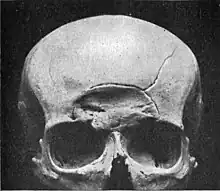

A piece of a skull with a depressed skull fracture

Depressed

Depressed skull fracture.

A depressed skull fracture is a type of fracture usually resulting from blunt force trauma, such as getting struck with a hammer, rock or getting kicked in the head. These types of fractures—which occur in 11% of severe head injuries—are comminuted fractures in which broken bones displace inward. Depressed skull fractures present a high risk of increased pressure on the brain, or a hemorrhage to the brain that crushes the delicate tissue.

Compound depressed skull fractures occur when there is a laceration over the fracture, putting the internal cranial cavity in contact with the outside environment, increasing the risk of contamination and infection. In complex depressed fractures, the dura mater is torn. Depressed skull fractures may require surgery to lift the bones off the brain if they are pressing on it by making burr holes on the adjacent normal skull.[3]